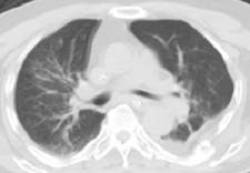

1.重症肺炎;

01.控制肺部感染

患者为多重耐药菌感染,根据相关检查结果及用药经验调整抗菌药物应用,总体原则以敏感、足量、联合为准。

03.集束化气道管理

反复的肺部感染很大程度上与气道功能障碍有关,有效的气道管理可明显降低肺部感染的发生。多学科联合会诊(MDT)提出改进气道管理方案,主要包括:气道湿化、气管套管管理、口腔护理、气切口护理、按需吸痰、气道廓清技术、体位引流、环境消毒等。经集束化气道管理后,患者痰液明显减少,肺部感染控制。

经过2月的治疗,患者生命体征稳定,无明显咳嗽、咳痰,血氧饱和度明显改善,顺利脱氧,吞咽功能好转,少量饮水(5ml)无明显呛咳,双下肺湿性啰音较前减少,血红蛋白及白蛋白明显增加,营养状况较前好转。拔管各项指征达标,成功拔出气管套管。